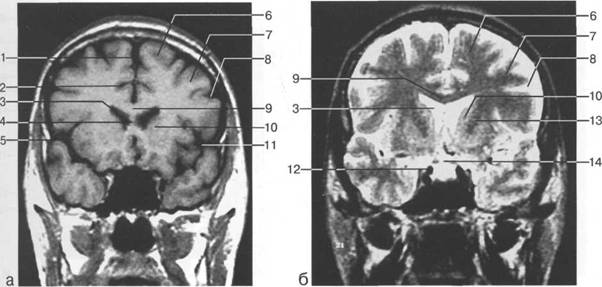

височная доля; 17 - полушарие мозжечка; 18 - |

мие; 26 - поясная борозда; 27 - головка хвостатого ядра; 28 - бледный шар; 29 - височный рог боково

цистерна четверохолмия; 14 -прямой синус; 15 -лобный рог; 16 - головка хвостатого ядра; 17 -перед

теменно-затылочная борозда; 11 - семиовальные